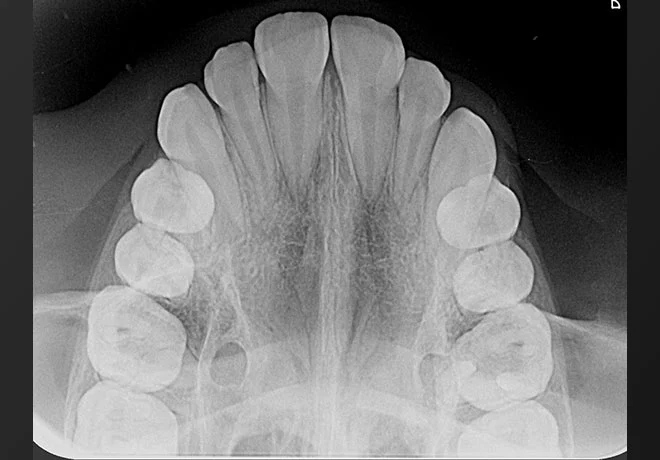

Filme Radiográfico Oclusal

O filme oclusal é maior (tamanho 4) e cobre áreas mais amplas da arcada dentária.

É indicado para identificar dentes inclusos, avaliar fraturas, acompanhar lesões extensas e investigar alterações de desenvolvimento ósseo.

Também auxilia na localização de corpos estranhos na cavidade bucal.